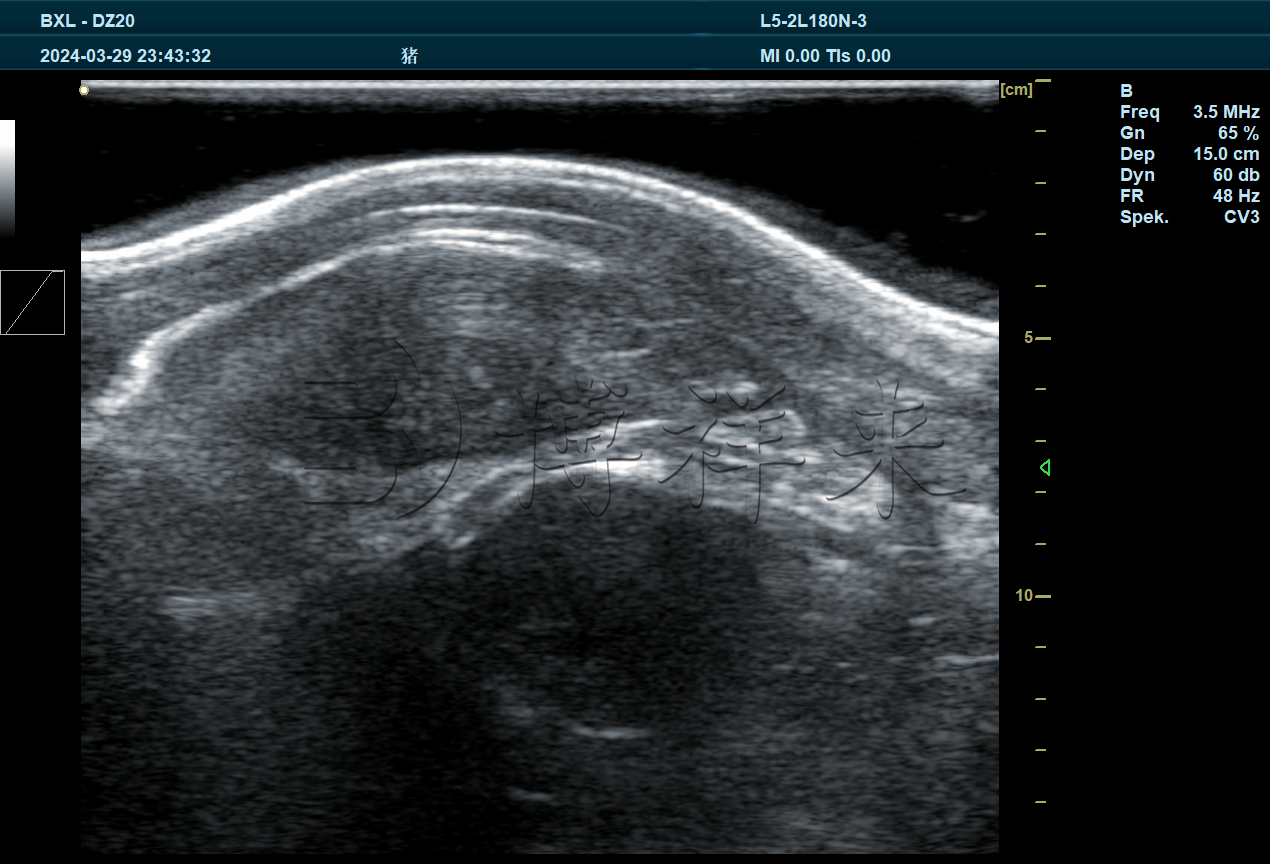

背膘仪是一种专用于猪只体况评估的便携式设备,主要通过超声波探头检测猪只背部脂肪层的厚度。它的基本原理与兽用B超相似,利用声波在组织中的传播和反射特性,测量皮下脂肪层与肌肉层之间的距离,从而得出

背膘厚度数据。

作为专业的兽用B超机厂家,我们在研发过程中不断探索多功能一体化设备的可能性。兽用B超机已经集成了背膘测量功能,通过更高频率的探头和定制化的测量软件模块,不仅能进行常规的怀孕检测、组织结构观察,还可实现猪背膘厚度检测吉彩网,为养殖户提供“一机多用”的高性价比解决方案。